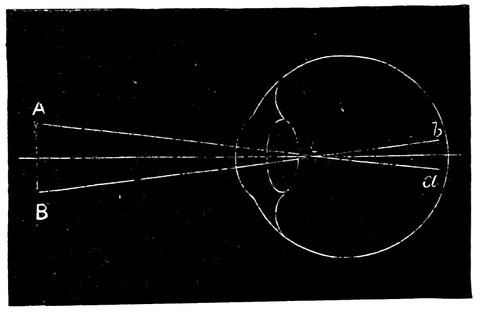

| 33. | Action of eye in formation of images | 68 |

| 35. | Diagram showing path of rays when viewing an object at an easy distance | 70 |